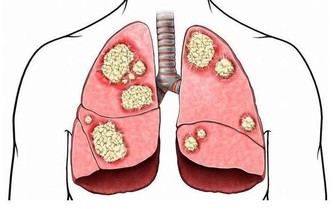

肺部是呼吸系統重要的器官,人們的輕鬆的呼吸、乾淨的血液都依靠肺部的運行。當肺部出現了健康問題,對於整個身體健康是有很大影響的,甚至會危及到生命,所以及時知曉肺部的求救信號是非常重要的。睡覺時有哪些異常情況是肺在求救呢?接下來讓我們一起來了解一下。

睡覺的時候哪些異常情況是肺在求救呢?

肺部受損是一件比較重大的事,出現了肺部疾病也不要拖延,一定要及早治療,這樣才能把後果盡量的降到最低。